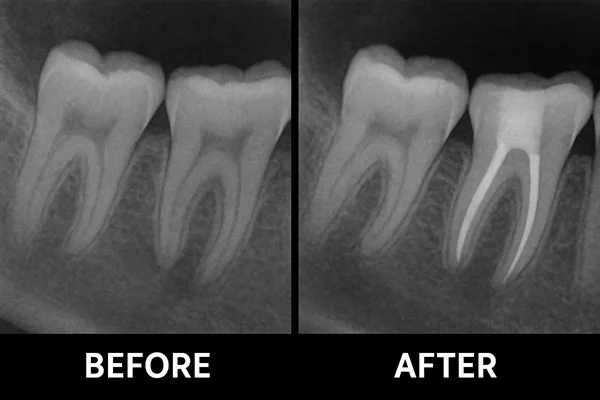

- The infected tissue inside the tooth is carefully removed and the canals are cleaned and shaped.

- The cleaned canals are filled and sealed to prevent further infection.

- Finally, a crown or filling is placed to restore the tooth’s strength and function.